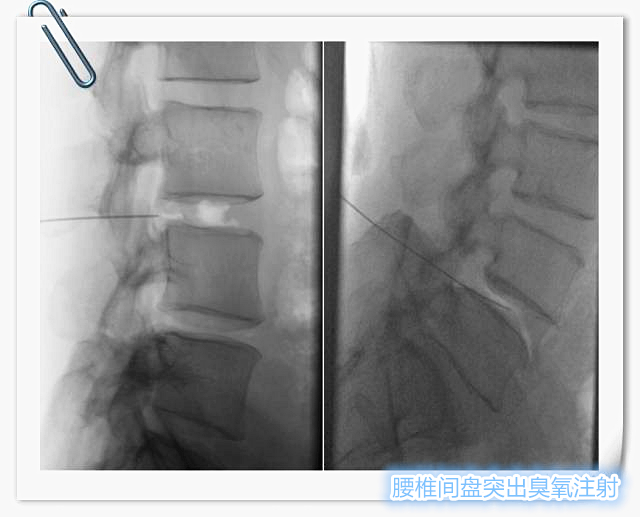

腰椎间盘臭氧注射术

腰椎间盘臭氧注射术 已是国内外临床成熟于治疗腰椎间盘突出症的微创方法。主要原理是将臭氧注射人椎间盘内,破坏髓核中的蛋白多糖,使髓核变性、坏死、萎缩,从而缓解对神经根的压迫。同时臭氧尚有止痛、消除神经根无菌性炎症、减轻免疫反应等优点。椎旁注射臭氧能够缓解腰大肌痉挛及减少脂肪化,对于维持脊柱的稳定性有重要意义。在各种治疗椎间盘突出的方法中,臭氧治疗是创伤小、并发症少、安全有效的治疗方式。

在DSA实时引导下,精确穿刺病变椎间盘,注射臭氧进行病变椎间盘髓核消融治疗,后退针至椎旁组织注射臭氧及消炎镇痛剂。

腰椎间盘髓核臭氧消融及脊神经根阻滞术